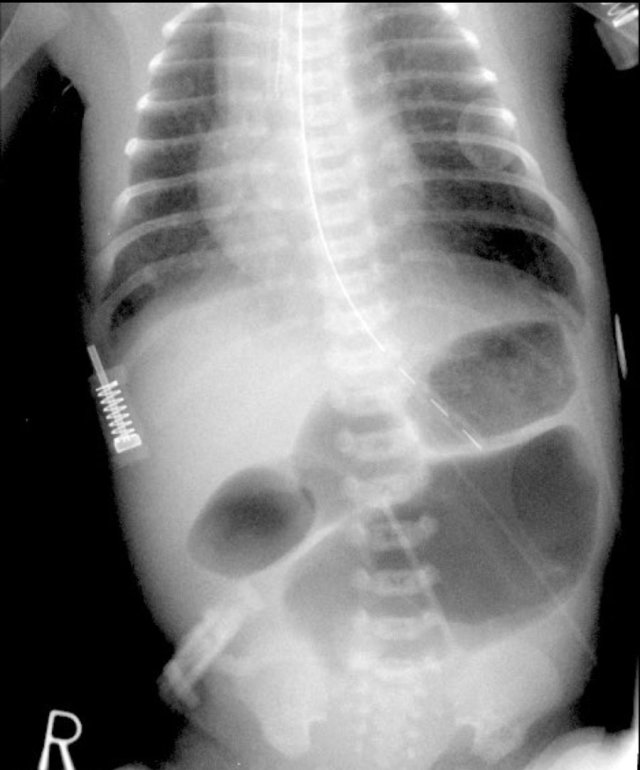

Here images of a neonate who developed NEC.

At this early stage the radiograph only shows non-specific bowel dilatation.

At this stage you cannot make the diagnosis.